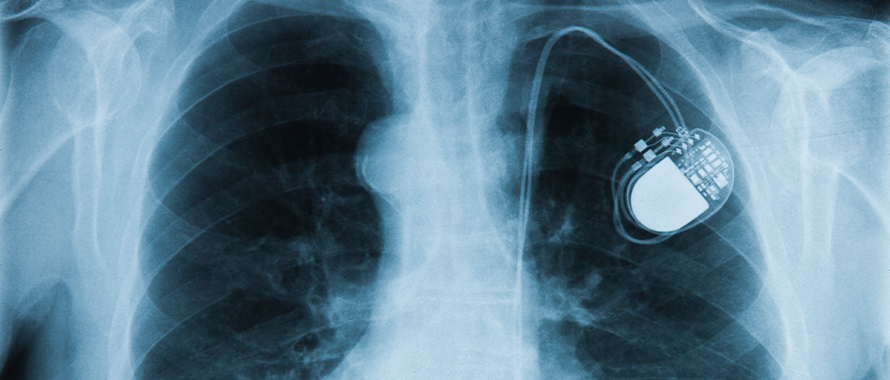

On October 1, the Federal Drug Administration (FDA) issued a warning about the so-called URGENT/11 cybersecurity flaws that leave certain Wi-Fi-enabled medical devices vulnerable to being remote-controlled by hackers, such as cardiac pacemakers, implantable cardioverter defibrillators (ICDs) or insulin pumps.

The FDA indicated that devices potentially at risk are those utilizing IPnet, a decades-old software application that enables wireless networking. According to the statement, a successful cyberattack could allow a hacker to remotely change a device’s function, cause a denial of service, information leak or logic flaw that could lead the device to malfunction.

Although estimates vary, The Pacemaker Club, an online community for those living with implanted cardiac devices, reports that 3 to 4 million people worldwide are living with pacemakers or other implanted cardiac devices. According to a June U.S. News and World Report guide to pacemakers, 400,000 pacemakers or ICDs are implanted in patients in the U.S. annually. The Canadian Institute for Health Information reported that 23,380 pacemakers were implanted in patients in Canada in 2017 and 2018.

Advances in technology have enabled medical devices to transmit vital statistics and data to physicians for monitoring. A patient’s heart rate can be assessed and the device adjusted when needed to ensure optimal therapeutic benefits and health benchmarks are achieved. Unfortunately, security flaws in this same technology can also allow hackers to take control of devices or access patients’ confidential medical data.

In March, the FDA issued a safety alert detailing the cybersecurity vulnerabilities identified in the Conexus wireless telemetry technology used in at least 20 models of Medtronic’s ICDs and cardiac resynchronization therapy defibrillators (CRT-Ds) as well as clinic programmers and home monitors. The Conexus technology in these models does not utilize encryption, authentication or authorization, which could allow unauthorized individuals to access and manipulate them. An estimated 750,000 devices may be affected by this security flaw.